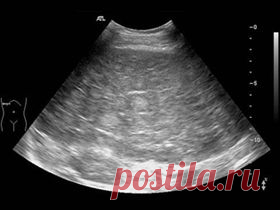

Подготовка к УЗИ органов брюшной полости. Что требуется от пациента? | Сам себе Гиппократ